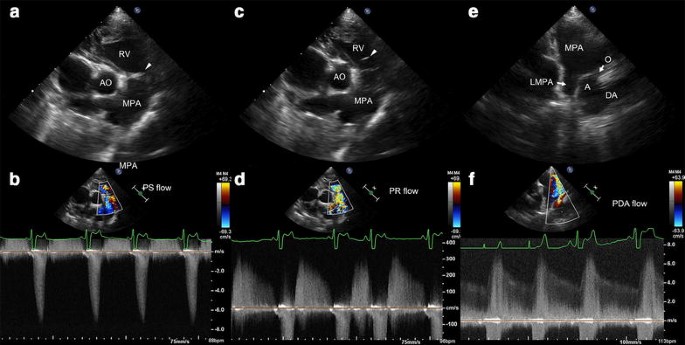

pda heart echo sale